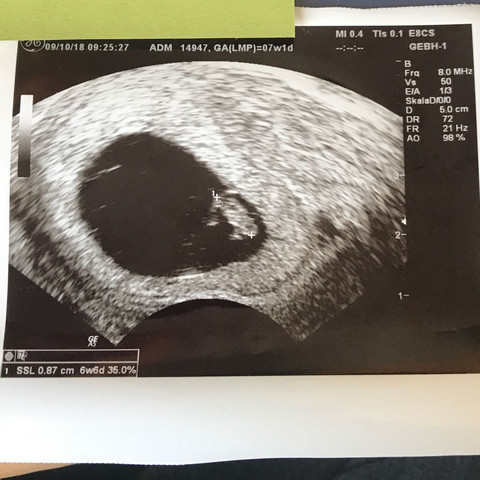

7+3 Ssw Ultraschall

Du kannst somit bereits in der 7SSW mit dem Ultraschall das Herz deines Kindes sehen und hören So sah der Ultraschall in der 6SSW aus >>> Ultraschall 6SSW Das Ultraschallbild in der 7SSW sieht so aus Dieses Bild zeigt einen Ultraschall einer Frau in der 7Schwangerschaftswoche Man sieht den Kopf, der auf der Brust liegt und erkennt den. 73 Ultraschall Schwanger wer noch?. 7 3 ssw ultraschall Was passiert in der 7 SSW?.

Du kannst somit bereits in der 7SSW mit dem Ultraschall das Herz deines Kindes sehen und hören So sah der Ultraschall in der 6SSW aus >>> Ultraschall 6SSW Das Ultraschallbild in der 7SSW sieht so aus Dieses Bild zeigt einen Ultraschall einer Frau in der 7Schwangerschaftswoche Man sieht den Kopf, der auf der Brust liegt und erkennt den. SSW auf dem Ultraschall zu erkennen ist In der 3 SSW hat der Embryo noch nicht mal die Größe von 1 mm erreicht Seine Aufgabe besteht nun darin, sich erfolgreich in die Gebärmutterschleimhaut einzunisten Sobald die Einnistung erfolgreich war, ist die Fruchthöhle ab der 4. SSW ist 8 Ultraschall in der 3 SSW Wer in der 3 Schwangerschaftswoche einen Termin beim Frauenarzt hat und dort einen Ultraschall machen lässt, wird noch nichts von einer Schwangerschaft sehen Die befruchtete Eizelle ist nicht von einer unbefruchteten zu unterscheiden und zudem viel zu klein.